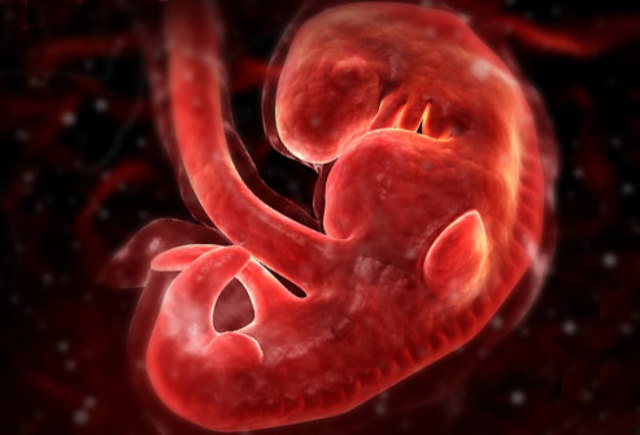

• development at 4 weeks

development at 4 weeks

baby developing structure that will eventually form is face and neck the heart and blood vessels continue to develop and the lungs stomach liver start to develop